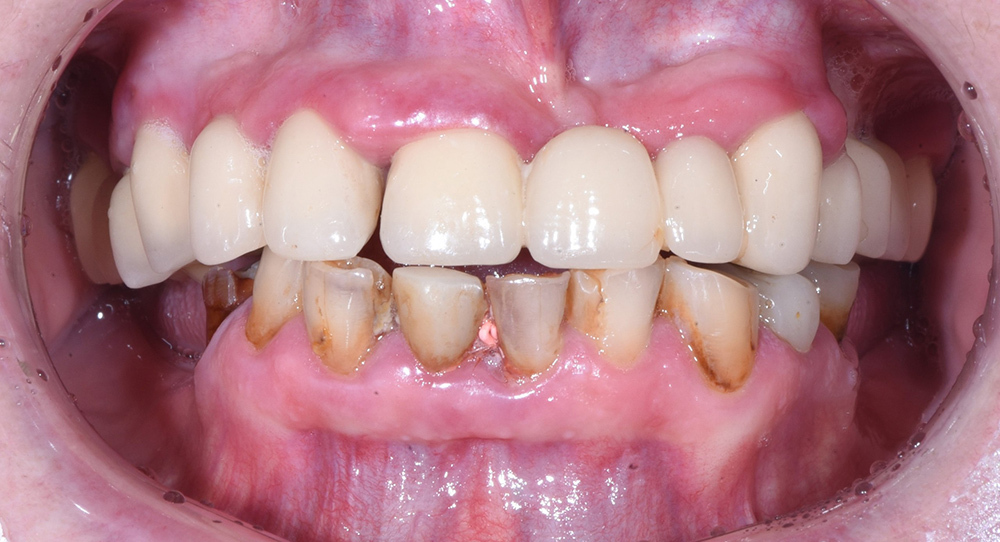

Тотальное восстановление зубов обеих челюстей